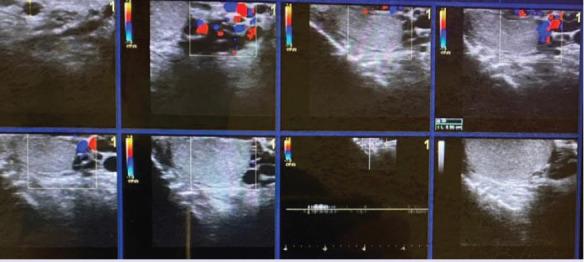

伴有睾丸外精索静脉曲张病例的睾丸内精索静脉曲张的区域分布。

Regional distribution of intratesticular varicoceles accompanying extratesticular varicocele cases.

Approximately 10,537 patients with scrotal pain and swelling who visited our hospital between August 2014 and May 2020 and underwent scrotal colour Doppler ultrasonography were included in this study. Of these patients, 2285 had ETV, and the remaining patients (n=8252) had other testicular pathologies such as acute-chronic torsion, testicular mass, orchitis, significant testicular atrophy, or isolated extratesticular varicocele, and were thus excluded from the study. Among the 2285 patients, only 20 had ITV.

Of the 20 patients with ITV, 2 had isolated ITV, and the remaining had ITV accompanying ETV, of whom only one had a right ETV. One patient had left testicular atrophy accompanying an isolated ITV. Among the ITV cases, subcapsular ITV was the most common (n=13), followed by central ITV (n=4) and subcapsular and hilar ITV (n=3). The patients' ages ranged from 18 to 30 years.

在20例ITV患者中,2例为孤立性ITV,其余患者为ITV伴发ETV,其中只有1例为右侧ETV。1例患者伴有孤立性ITV的左侧睾丸萎缩。在ITV病例中,最常见的是包膜下ITV(n = 13),其次是中央ITV(n = 4)和包膜下及肾门ITV(n = 3)。患者年龄在18至30岁之间。